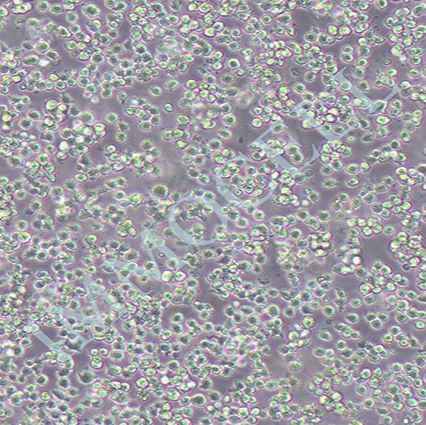

2) 形态:悬浮生长

3) 含量:>1x106 个/mL

a) 该细胞复苏后成活率较低,会出现大量死细胞和死细胞碎片,培养两周后有所好转。建议每1-2周对细胞进行1000rpm, 5mins离心,弃掉上清,加入新鲜完全培养液,可以去掉部分细胞碎片和颗粒。培养过程中会出现死细胞和细胞碎片,收到邮寄的活细胞的用户若发现培养物内有部分死细胞和细胞碎片,此为正常现象。

b) 细胞培养过程中会有轻微聚团,轻轻吹打开即可。当细胞密度较大或者培养液变黄时,需要及时进行半换液或者完全换液。

d) 请注意保持细胞密度在合适的范围(3x105 ~ 3x106 /ml),不能过稀。